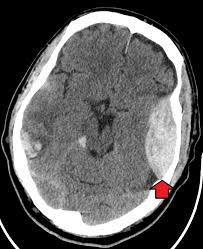

The most important symptoms of an EDH are: Confusion. Dizziness. Drowsiness or altered level of alertness. Enlarged pupil in one eye. Headache (severe) Head injury or trauma followed by loss of consciousness, a period of alertness, then rapid deterioration back to unconsciousness. Nausea or vomiting.